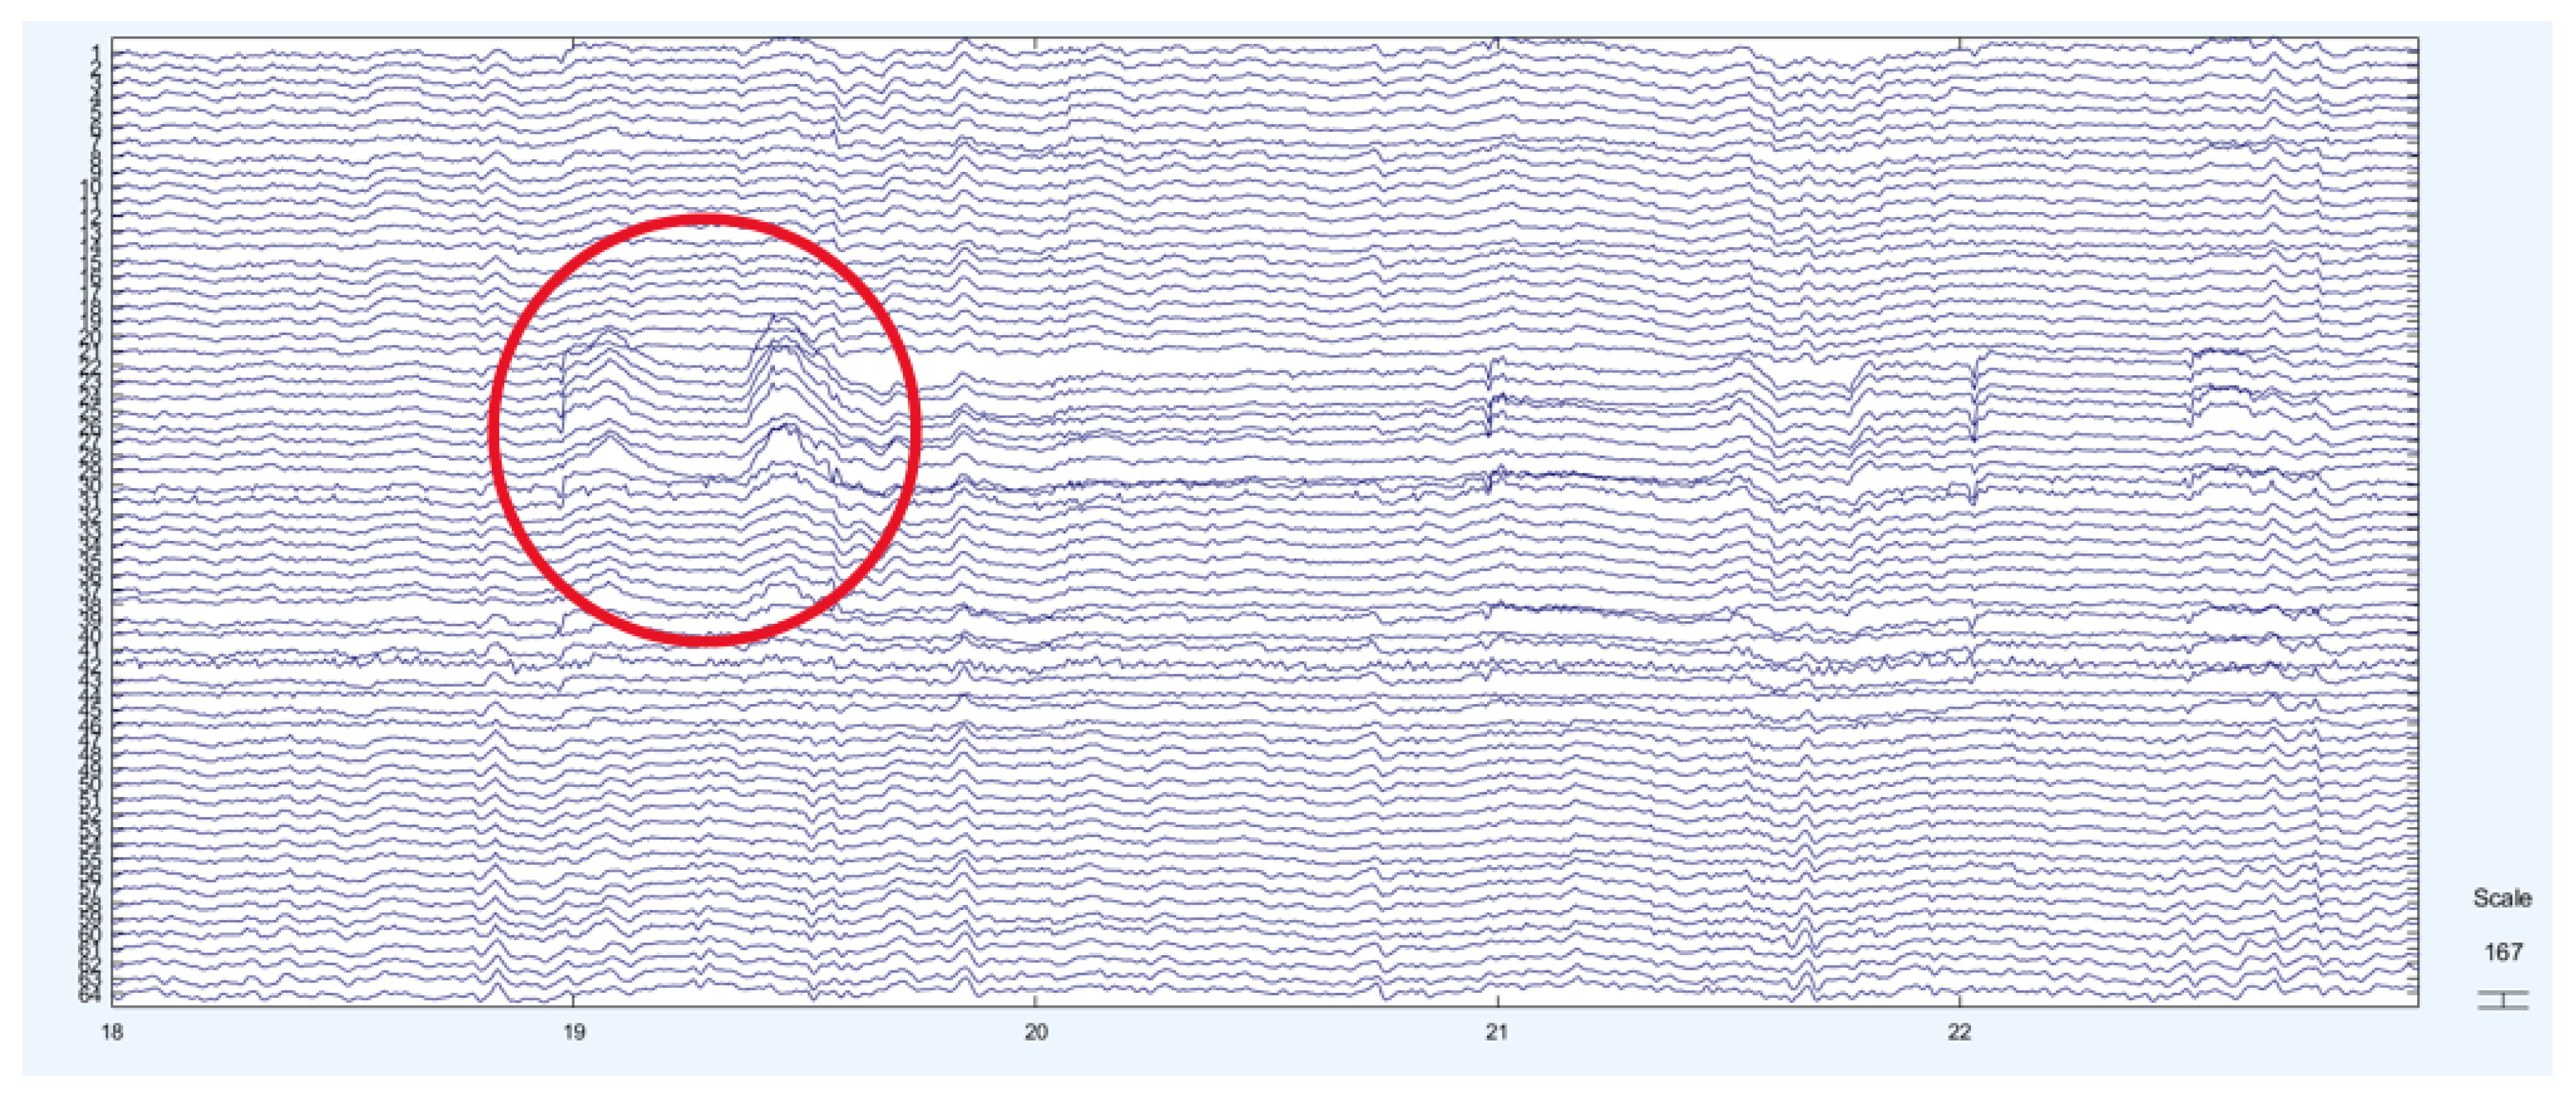

2. Materials and Methods

2.4. Wavelet Transform

3. Results